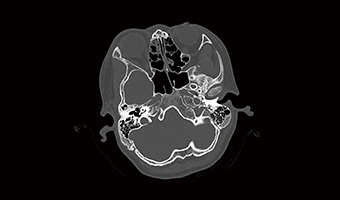

Application Images